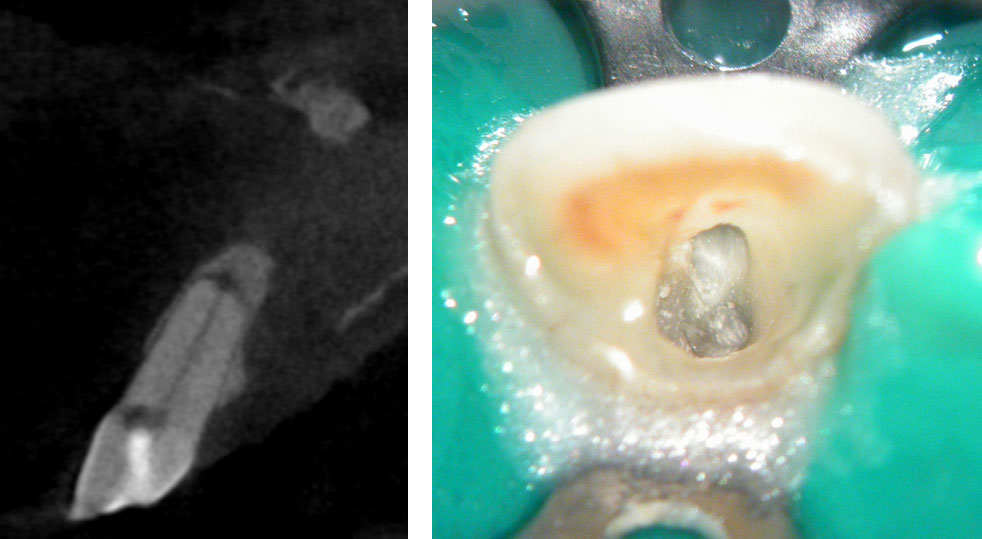

Pre-op

Pain in mandibular first molar after endo. Previous dentist unable to locate mesial canals. Obturated only the distal canal. Patient has generalized periodontal problems as well.

Pre-op, EDTA for 1 minute, After 1 minute EDTA

Red arrows show the two “white spots” indicating the calcified mesial canals.

Missed second distal canal (red arrow)

Pre-op & Post-op